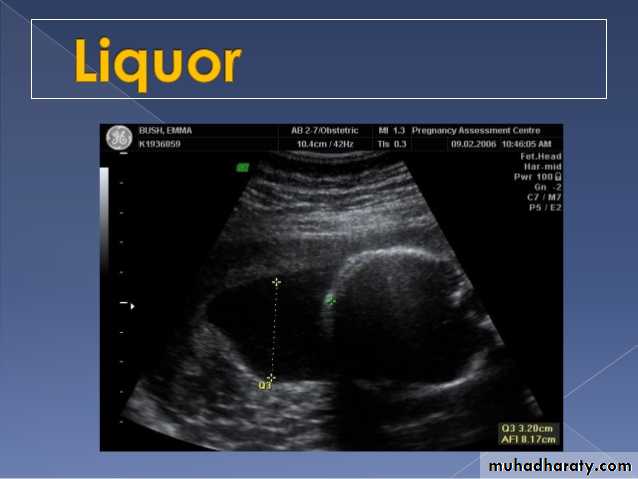

Poly hydraminous :

Poly hydraminos refers to a situation where the amniotic fluid volume is more than expected for gestational age.It is generally defined as:

amniotic fluid index (AFI) > 25 cm

largest fluid pocket depth (maximal vertical pocket (MVP)) greater than 8 cm

overall amniotic fluid volume larger than 1500-2000 cc3